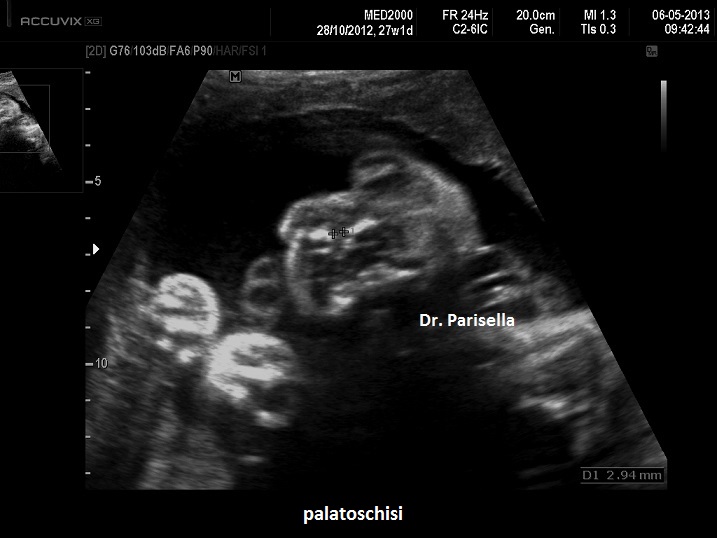

• labiopalatoschisi,

La diagnosi prenatale è difficilissima, i segni ecografici da ricercare sono:

1. ventricolomegalia,

2. anomalie facciali (bozze frontali, ipertelorismo, naso a sella),

3. macrocefalia,

4. tumori multipli.